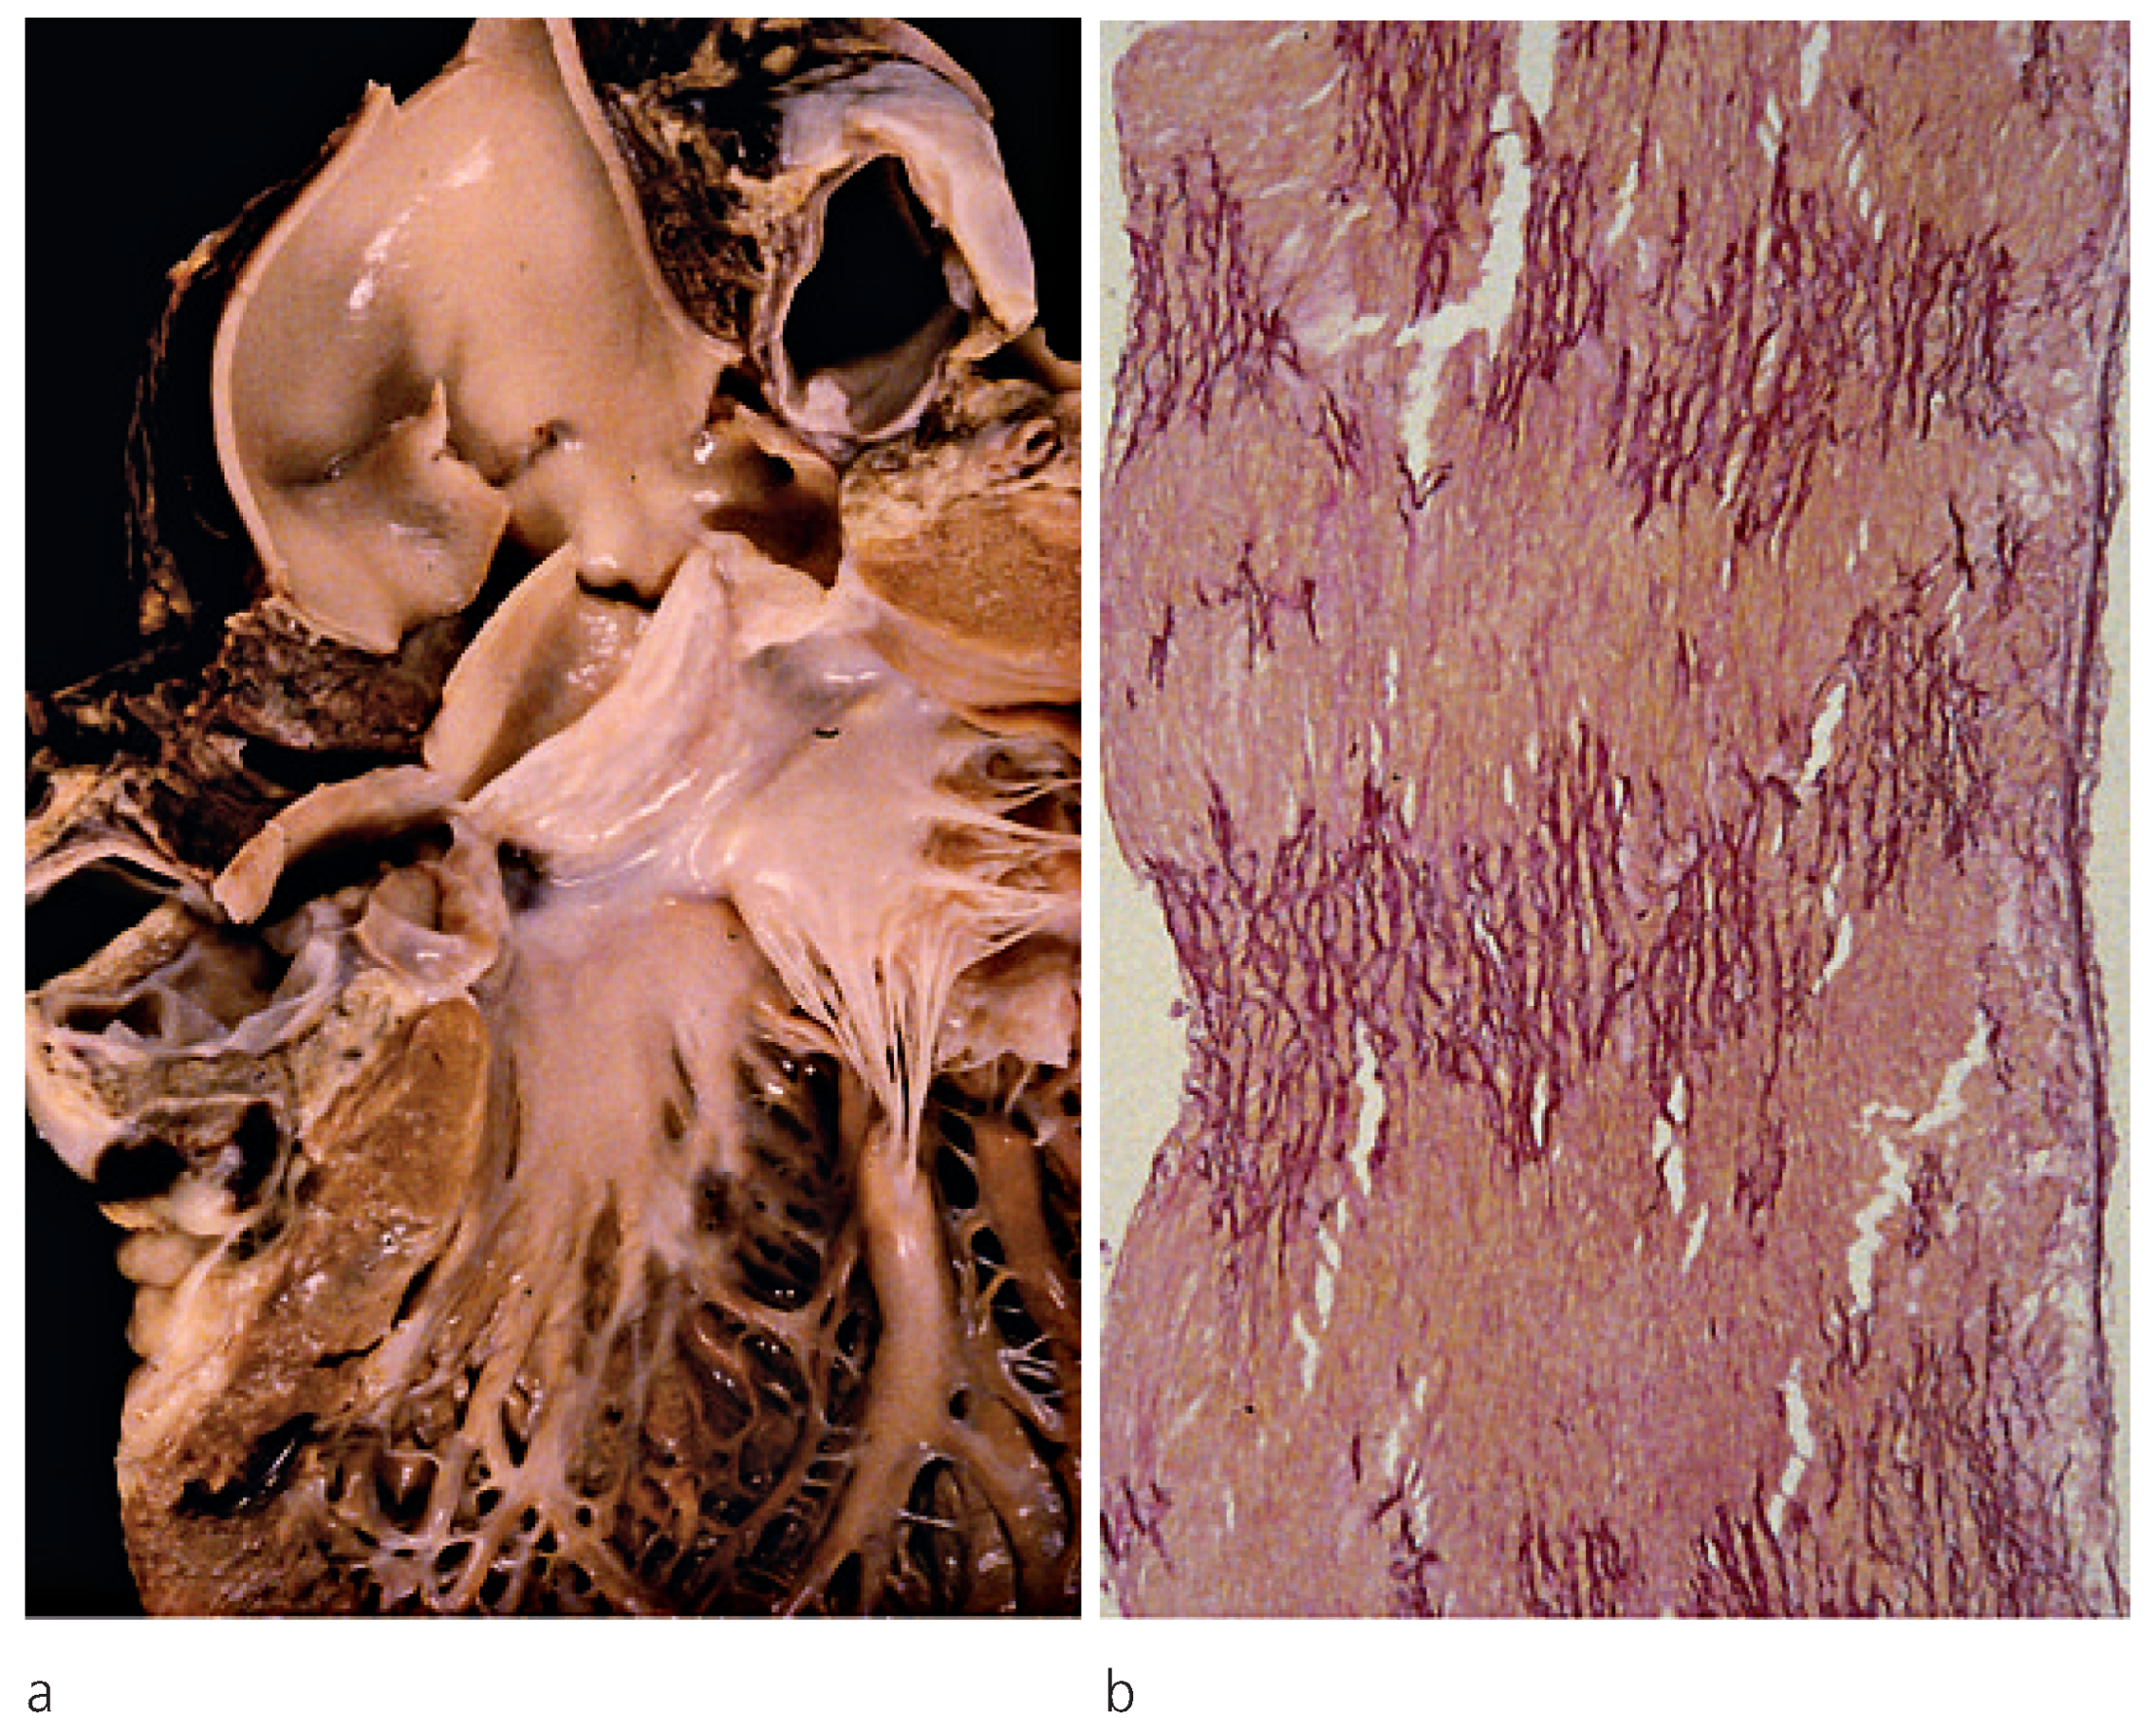

Valves